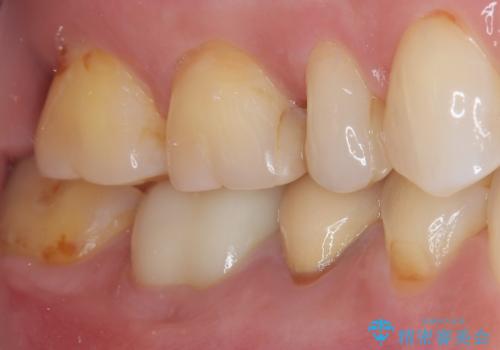

検診で見つかった齲蝕のセラミックインレー修復

- 検診で初期の齲蝕が見つかった患者様です。

これ以上神経の治療や被せものになりたくないため、初期のうちにしっかりとした治療をしたいとのことでした。

齲蝕をしっかりと除去して、精度の高いシリコーンによる型どりを行いセラミックインレーで修復しました。

唾液による接着阻害を防ぐために、ラバーダム防湿を行っています。